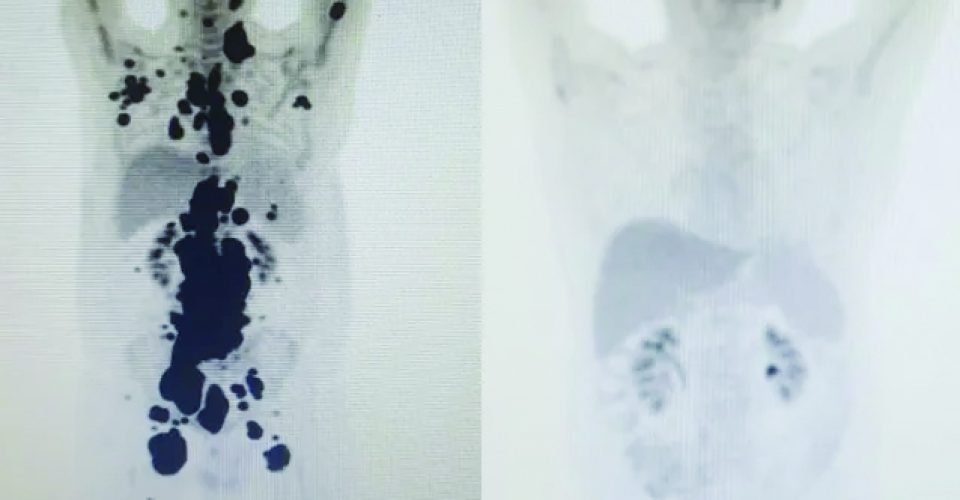

Paulo Peregrino lutava contra o câncer há 13 anos e estava prestes a receber o tratamento por meio dos cuidados paliativos quando, em abril deste ano, foi submetido a um tratamento considerado revolucionário no combate à doença e, em apenas um mês, teve remissão completa do seu linfoma.

O publicitário, 61 anos, é o caso mais recente de remissão completa em curto período de tempo do grupo de estudos do Centro de Terapia Celular. O protocolo foi adotado pela USP, em parceria com o Instituto Butantan e o Hemocentro de Ribeirão Preto.

Paulo teve alta no último domingo (28), depois de ficar sob cuidados médicos no Hospital das Clínicas, da cidade de São Paulo. “A vitória não é só minha. É da fé, da ciência e da energia positiva das pessoas. Cada uma delas ajudou a colocar um paralelepípedo nesse caminho. A imagem prova com muita clareza, para qualquer pessoa, a gravidade do meu linfoma, e eu não tinha ideia de que era assim. Tenho certeza de que, pelo menos, terei, modestamente, passado esperança a quem tanto precisa.

Só quero que as informações e o conhecimento adquiridos com meu caso possam servir a outros pacientes no futuro”, declarou, nas redes sociais